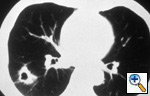

LUNG

CANCER

A Handbook for Staging, Imaging, and Lymph Node Classification

by Clifton F. Mountain, MD; Herman I.

Libshitz, MD; and Kay E. Hermes |